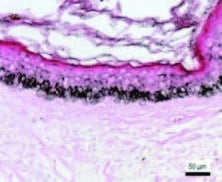

Epidermal melanin density in melasma before procedure

Reduction in epidermal melanin density 1 week after microneedling procedure

Cassiano et al., Indian Journal of Dermatology, Venereology and Leprology | Volume 85 | Issue 6 | November-December 2019